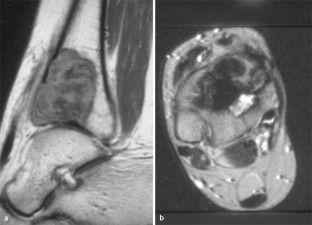

MRI morphology of bone tumors and tumor-like lesions

Für das Staging und die Charakterisierung von Knochentumoren und tumorähnlichen Läsionen ist in der Magnetresonanztomographie (MRT) der Einsatz von Spinechosequenzen erforderlich. Die MRT hat nur einen geringen Stellenwert in der Bestimmung der Dignität. Obwohl viele Knochentumoren und tumorähnliche Läsionen eine vergleichbare Morphologie in dieser bildgebenden Modalität aufweisen, können einige Tumorentitäten mittels MRT recht zuverlässig diagnostiziert werden. Hierzu zählen Knorpeltumoren, die solitäre und aneurysmatische Knochenzyste, der Riesenzelltumor, fetthaltige Läsionen und bis zu einem gewissen Grad auch das Osteoidosteom und das Osteoblastom. Es werden praktische Tipps gegeben, wann bei Tumorverdacht die MRT eingesetzt werden sollte, wie bei einem zufällig bei einer MRT gefundenen Tumor die Untersuchung modifiziert werden sollte und welcher Tumor vorliegen könnte.

Spin-echo sequences are mandatory at MRI for staging and characterization of bone tumors and tumor-like lesions. MRI is of minor value in the estimation of the malignant potential of an osseous lesion. Although many bone tumors and tumor-like lesions present similar morphology at MRI, some entities can be diagnosed with good reliability. These include chondrogenic tumors, solitary and aneurysmal bone cysts, giant cell tumors, lesions containing fatty tissue and, to a certain extent, osteoid-osteomas and osteoblastomas. Practical advice is given regarding when to perform a MRI study in cases of tumor suspicion. Further advices are given for cases a tumor is found incidentally at a MRI study, how to modify the study and which kind of tumor may be present.